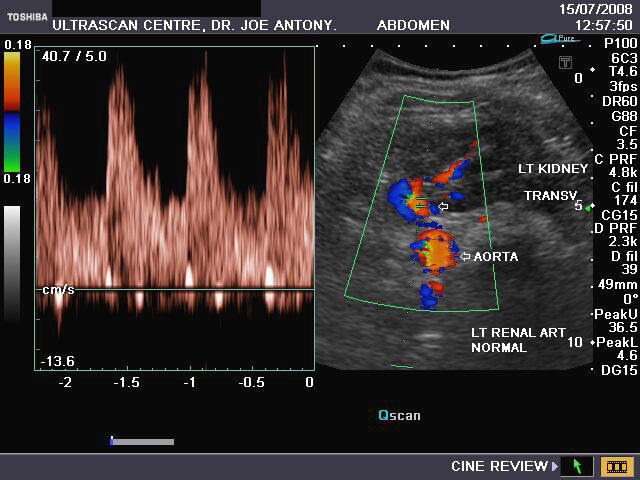

It takes patience and favourable imaging conditions (like thin abdominal wall and patient cooperation) to locate the renal arteries and veins by color doppler and even more difficult to get a spectral waveform tracing of the vessels. The upper few color doppler images show the left renal artery as it emerges from the abdominal aorta and enters the renal hilum. The lower few images show the right renal artery and right renal vein. Spectral tracing shows typical normal arterial and venous flow patterns. Ultrasound and color doppler images taken using a Toshiba Nemio XG color doppler machine by Joe Antony, MD, Cochin, India.